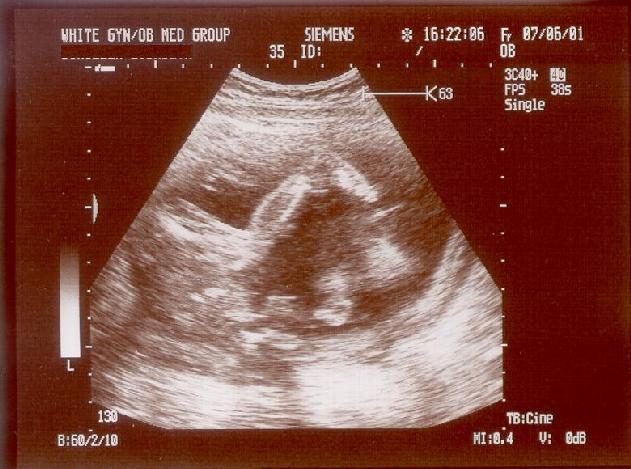

This is a more complete image of the whole guy: He's lying on his back and the foot and leg are quite visible. The toes are almost touching the forehead - if you squint a little, you can make out his skull with pronounced cheeks.